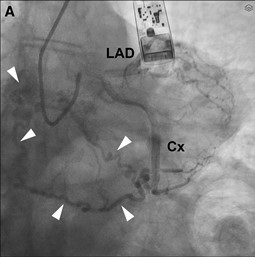

POSTER PRÆSENTERET VED DRS 2025

Vores introduktionslæge Shahad er gennem største delen af sit forløb, og har… Læs mere